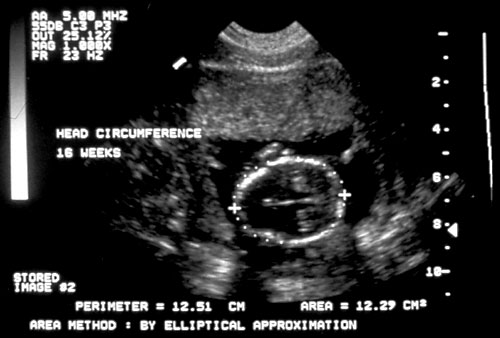

- Biparietal Diameter (BPD)/Head Circumference (HC)/Intracranial Anatomy — Ventricles/Atria/Posterior Fossa

Measurements from outer edge at superior margin to inner margin at inferior margin to correct for fetal skull thickness (left). Proper measurement of head circumference (right). - Clinically meaningless, unless multiple parameters are measured and evaluated.

- Measuring BPD/HC

- Axial plane at level of septum cavum pellucidum and thalamic nuclei. (Shepard M, Filly RA. A standardized plane for bieparietal diameter measurement. J Ultrasound Med 1982;1(4):145-50.)